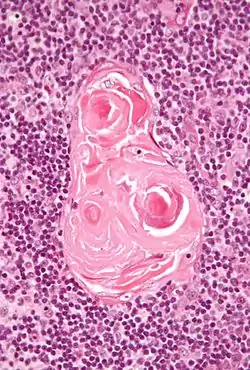

In the medulla, the network of epithelial cells is coarser than in the cortex, and the lymphoid cells are relatively fewer in number.[1] Concentric, nest-like bodies called Hassall's corpuscles (also called thymic corpuscles) are formed by aggregations of the medullary epithelial cells.[3] These are concentric, layered whorls of epithelial cells that increase in number throughout life.[1] They are the remains of the epithelial tubes, which grow out from the third pharyngeal pouches of the embryo to form the thymus.[6]